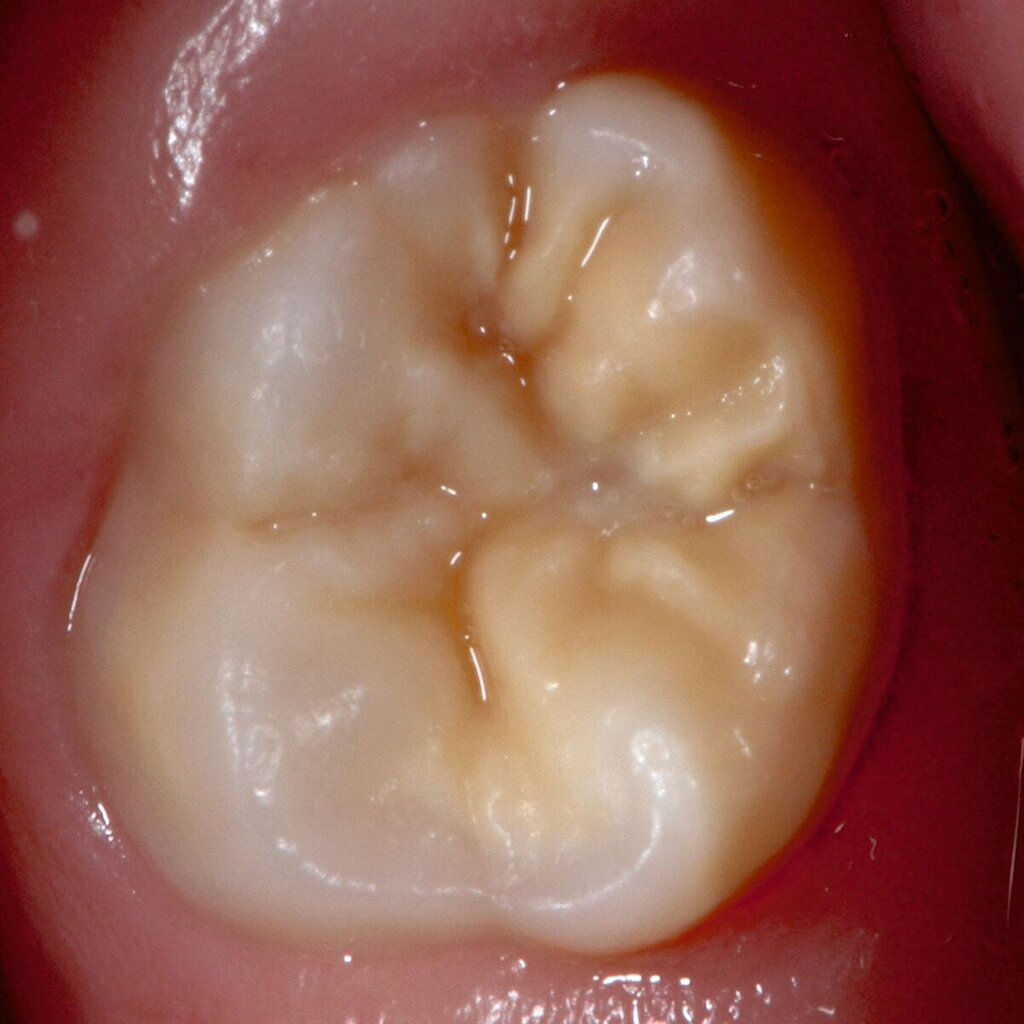

Das klinische Erscheinungsbild an bleibenden Zähnen zeigt typischerweise weißlich-gelbe bis gelblich-braune Opazitäten, die zumindest in einigen Bereichen durch eine scharfe Abgrenzung (engl.:„demarcated opacities“) zum gesunden Zahnschmelz charakterisiert sind (Abbildungen 3 und 4). Die abgegrenzten Hypomineralisationen befinden sich mehrheitlich im Bereich der inzisalen Kronenhälfte unabhängig von dem Auftreten an Front- oder Seitenzähnen. Die Ausprägung am Zahn kann dabei auf einzelne Areale oder Höcker begrenzt sein.

Bei einer schwerwiegenderen Ausprägung sind Zahnflächen vollständig betroffen, mitunter alle Zahnflächen an einem Zahn. Die Verteilung in der Dentition beziehungsweise an den Indexzähnen ist gleichermaßen variabel und betrifft nicht nur die Defektgröße, sondern auch die Farbe und Festigkeit. Was die Festigkeit betrifft, gilt als die Faustregel: Je dunkler die Farbe des Schmelzes, umso weicher beziehungsweise poröser und damit minderwertiger wird dessen Qualität sein. Damit reduziert sich seine kaufunktionelle Belastungsfähigkeit, was insbesondere an ersten bleibenden Molaren von klinischer Relevanz ist.

Für die Dokumentation und Klassifikation der MIH wurden verschiedene Systeme vorgeschlagen. Als historisch und veraltet gilt der (modifizierte) DDE-Index. Demgegenüber haben die Kriterien der EAPD – abgegrenzte Opazitäten (Abbildung 3 und 4), Schmelzeinbrüche (Abbildung 5), atypische Restaurationen (Abbildung 6) – mittlerweile die weiteste Verbreitung gefunden. Diese wurden 2003 erstmals zur Beschreibung der MIH auf empirischer Basis publiziert [Weerheijm et al., 2003] und den Jahren 2010 und 2022 im Rahmen der damaligen MIH-Workshops bestätigt [Lygidakis et al., 2010; 2022].